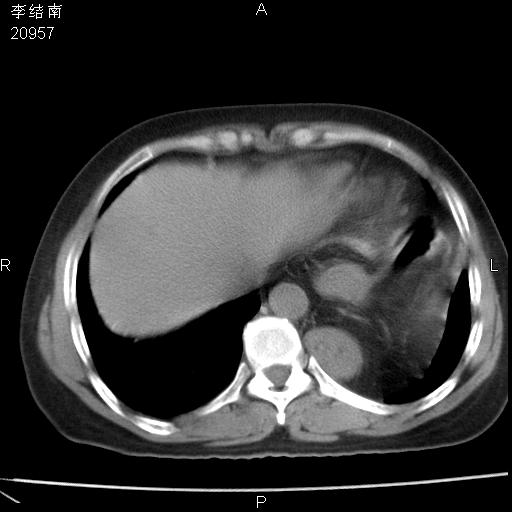

患者女,45岁,以右侧腰部包块来就诊,局部有压痛,皮肤颜色正常。因为是熟人扫的范围较大,患者有胆结石,胆源性胰腺炎病史。请大家看看,有手术病理。

可能大家觉得片子的质量不好,当时是做下腹部扫描,所以没有常规喝水,右腹壁的病灶当时是,密度不均有钙化影,局部骨质没见破坏,肝脏应该是受压的表现,所以当时考虑为腹壁的良性占位,各位老师考虑的神经源性肿瘤,我当时还真没想到,胰腺是胰腺炎治疗后改变.膈脚旁的混杂密度包快不好考虑什么,到上级医院做增强(腹部)+肺部平扫后,发现腹壁的病灶呈不均匀性强化局部可见囊性灶,当时考虑为腹壁结核,最具戏剧性的是膈脚旁的混杂密度灶确是胃的一部分,而腹壁的病灶确是脂肪瘤(简直不可思议)但是我亲眼所见在我们县医院开的.

很不好意思 ,患者后来手术切口裂开,临床医生作了病理证实是腹壁结核。

[病理诊断] CT13183腹壁结核!